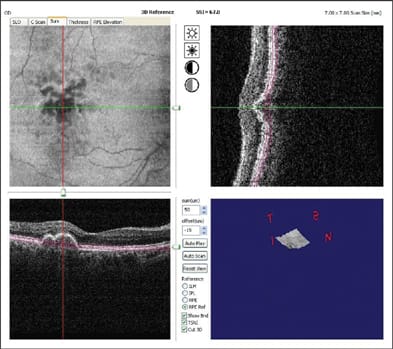

Besides the technical terms, there are even more terms introduced for marketing purposes. Topcon uses the name "3D OCT" to emphasize the fact that FD-OCT is able to acquire a 3D data within a few seconds. The 3D data can then be viewed by oblique cut-away (Figure 3), scrollthrough or fly-through of successive sections, en face project and C-scan. All FD-OCT systems on the market offer raster scan acquisition of 3D data and 3D viewing software. Zeiss calls the Cirrus system "HD-OCT" to emphasize the high-definition aspect of FD-OCT. With speeds ranging from 17,000 to 40,000 axial scans per second, the current generation of FD-OCT retinal scanners can all acquire a 1,000-line high-definition OCT image in a largely motion-free time frame (25 to 59 milliseconds). So the distinction is more in marketing emphasis than performance.

Figure 3. Cut-away 3D view of the macula taken with the Optovue RTVue system.